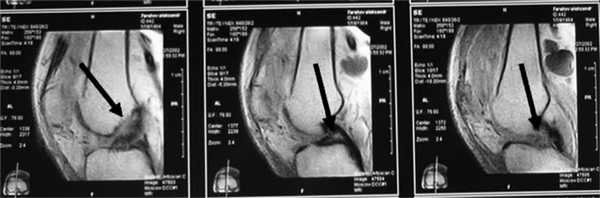

Все пациенты как с хронической патологией коленного сустава, так и с острой его травмой были обследованы с помощью МРТ-диагностики, что резко повысило качество дооперационной диагностики внутрисуставных повреждений коленного сустава. МРТ-диагностику выполняли на томографах 3—4-го поколения, с напряжением магнитного поля свыше 1,5 Tesla, разрешающая способность которых позволяла визуализировать повреждения связочных структур, менисков, суставного хряща, костной ткани коленного сустава (рис. 1 и 2).

Рис. 2. МРТ старого повреждения ПКС коленного сустава. Стрелки указывают на зоны повреждения ПКС.